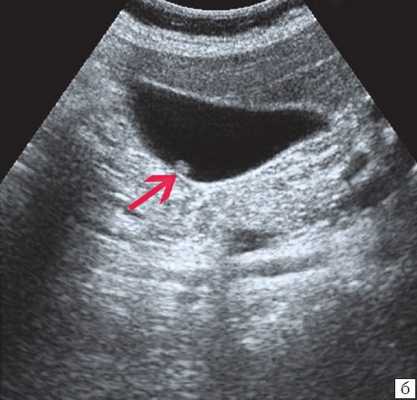

(Левый) На поперечном УЗ срезе определяется сладж, заполняющий желчный пузырь. Сладж имеет такую же эхогенность, как и печень, это состояние называют «гепатизацией».

(Правый) Положение пациента на левом боку. На продольном УЗ срезе визуализируется смещающийся книзу под действием гравитации сладж, напоминающий полип. Стенка желчного пузыря не изменена.